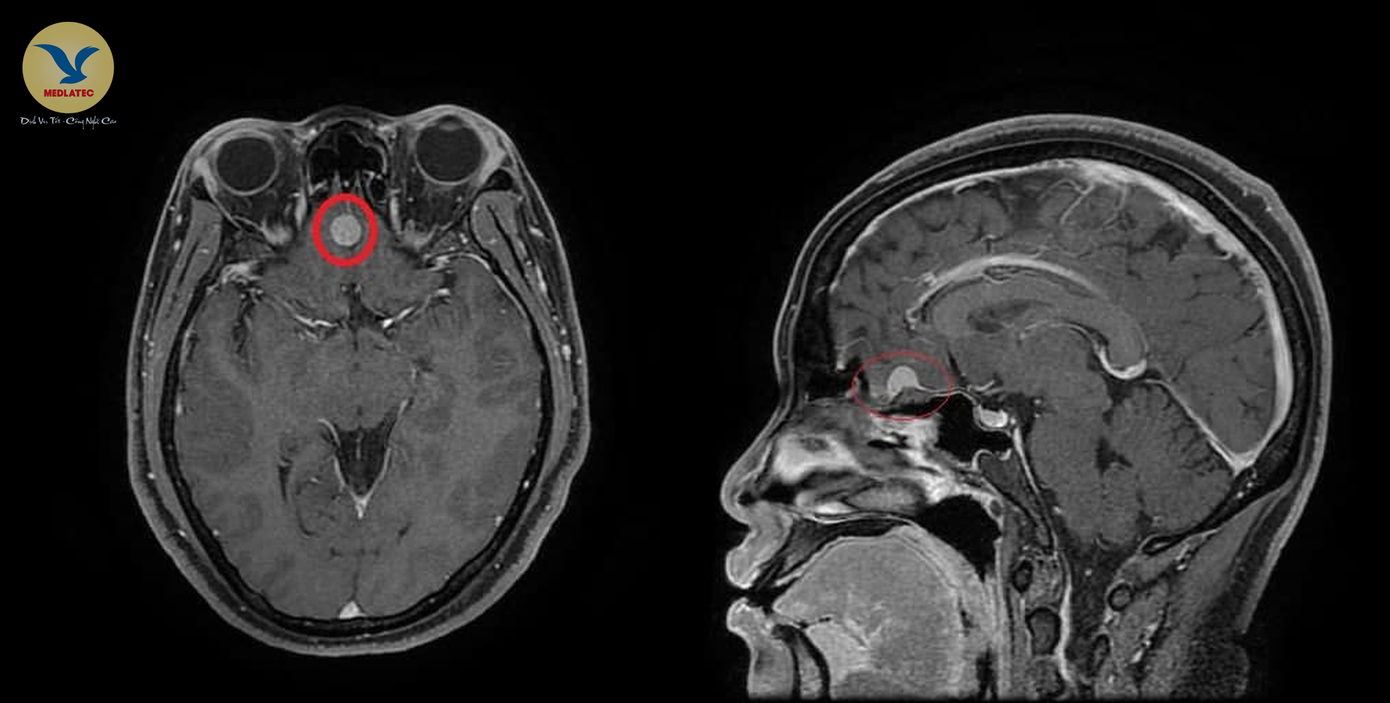

Hình ảnh khối u màng não kích thước khoảng 9x10mm vị trí liềm đại não trước của bệnh nhân T., trên hình ảnh chụp MRI

Qua quá trình thăm khám lâm sàng, chị T., không có triệu chứng bất thường điển hình, mà nổi bật là đau đầu, đau nhiều vùng đỉnh chẩm, đau lan ra sau gáy, thạc sĩ Chi chỉ định bệnh nhân chụp cộng hưởng từ (MRI) và phát phát hiện khối u màng não kích thước khoảng 9x10mm vị trí liềm đại não trước.